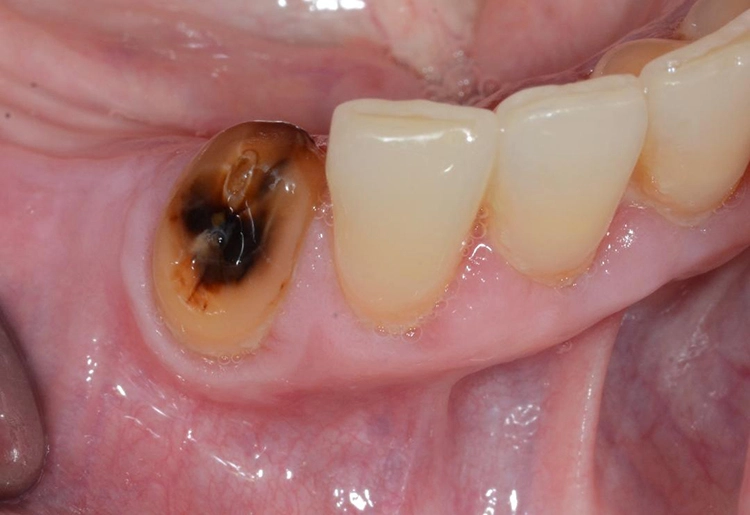

Bei einfachen zahnärztlich-chirurgischen Eingriffen ist die Regenerationsfähigkeit des Knochens deutlich gesenkt. Die Bezeichnung der medikamentenassoziierten Osteonekrose des Kiefers (MRONJ = „medication-related osteonecrosis of the jaw“) wird definiert durch folgende Punkte:

- mehr als 8 Wochen exponierter nekrotischer oder sondierbarer Kieferknochen

- laufende oder frühere Einnahme von antiresorptiven oder antiangiogenetischen Medikamenten

- keine Kopf-Hals-Radiatio in der Anamnese

| 1 | – exponierter oder sondierbarer, nekrotischer Knochen – asymptomatischer Befund – keine Anzeichen von Infektionen |

| 2 | – exponierter oder sondierbarer, nekrotischer Knochen, – symptomatischer Befund (Schmerzen, Entzündungszeichen) – Anzeichen von Infektionen |

| 3 | Zusätzlich zu Stadium 2 noch mindestens eines der folgenden Symptome: – exponierter nekrotischer Knochen, der sich auf benachbarte Regionen (Kieferhöhle, Jochbein, Unterkieferbasis) ausbreitet – pathologische Frakturen – extraorale Fisteln – Mund-Antrum-Verbindung (MAV) |

Die Stadien 0 und 1 können konservativ mit Spülungen und ggf. Antibiotikatherapie behandelt werden. Allerdings gilt es zu bedenken, dass nekrotischer Knochen nicht wieder vital wird und somit eine dauerhafte Infektionsquelle darstellt. In neueren Studien konnte deshalb auch gezeigt werden, dass nach chirurgischer Intervention, auch in den Stadien 0 und 1, eine deutlich höhere Heilungsrate verzeichnet werden konnte als bei rein konservativer Therapie [3,13,21].

Bei chirurgischer Intervention soll eine atraumatische OP-Technik angewendet werden. Dazu gehören das Glätten scharfer Knochenkanten im Sinne einer modellierenden Osteotomie und eine plastische Deckung der Wunden durch einen spannungsfreien Wundverschluss.